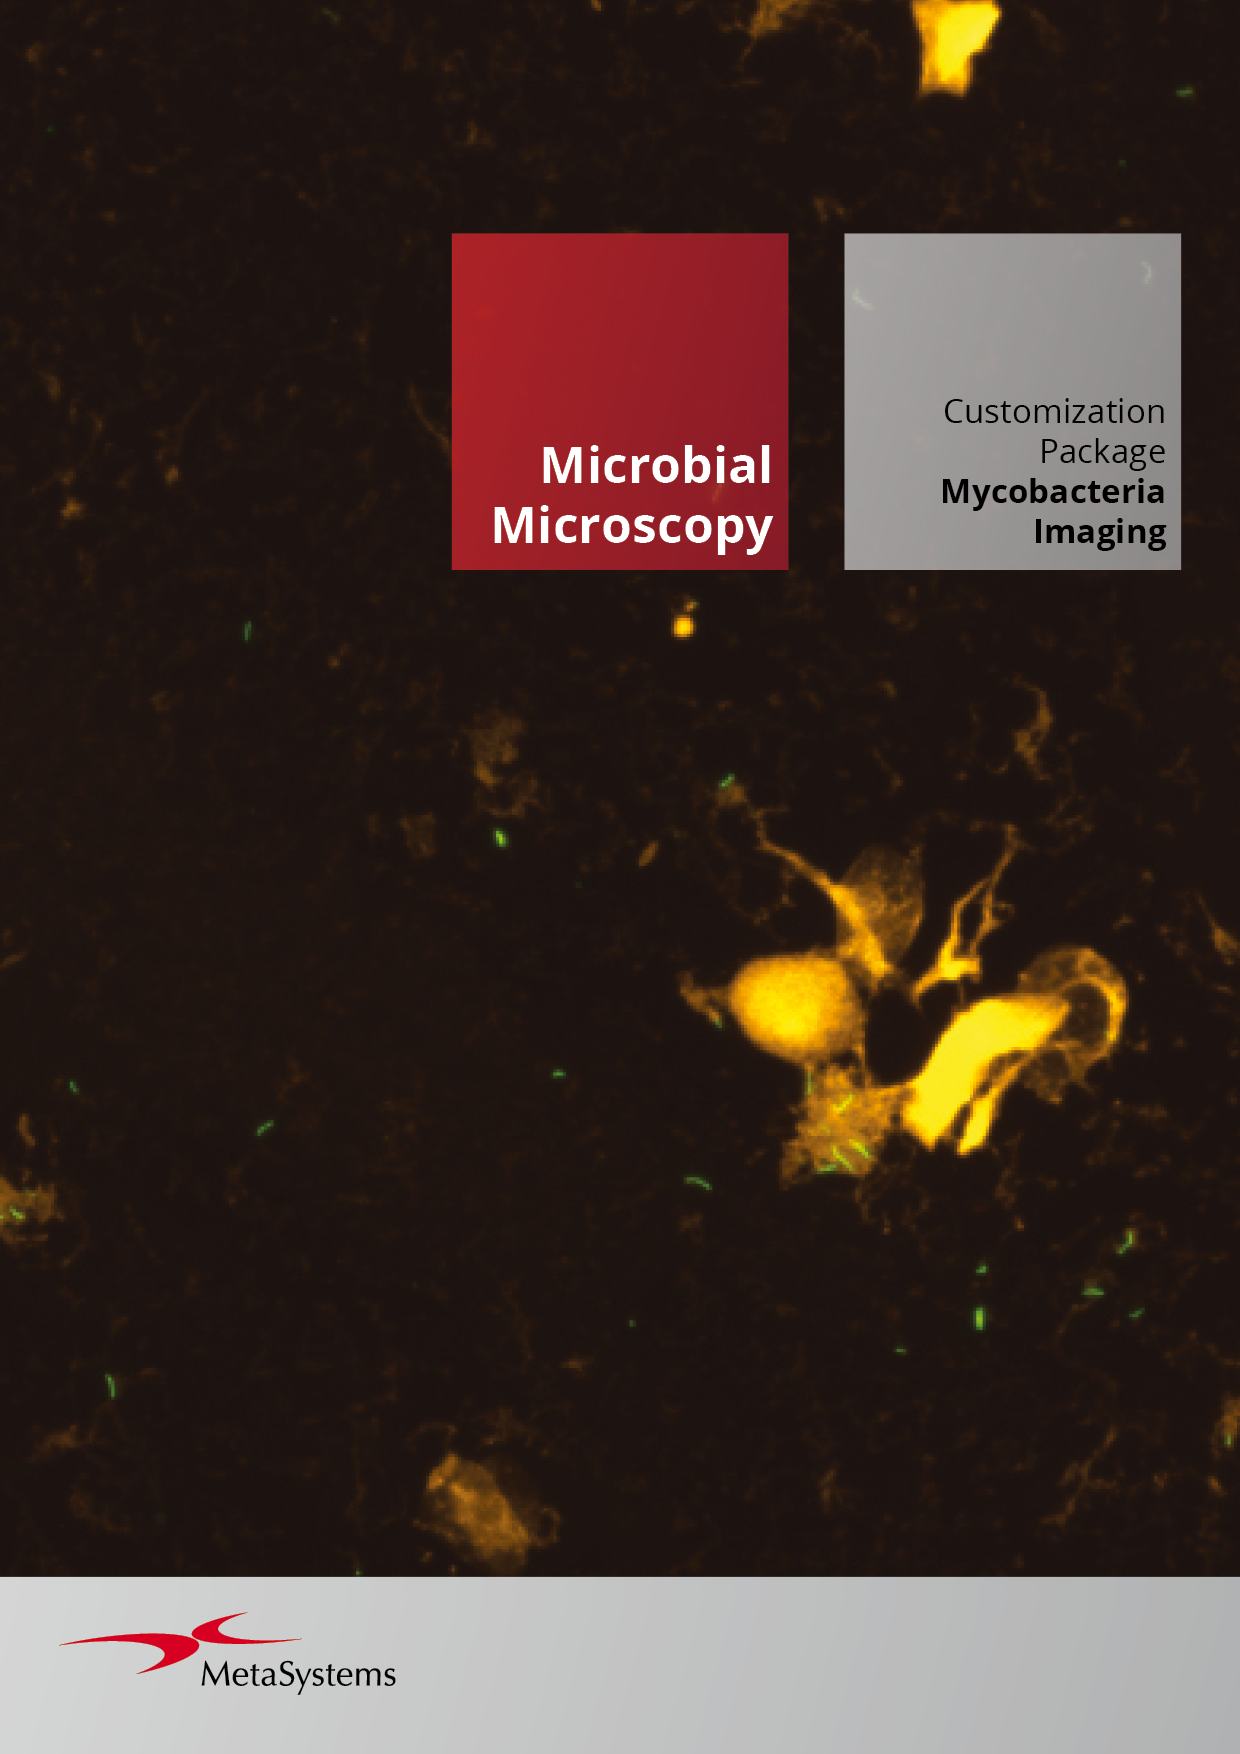

- Utilize various contrasting methods, including but not limited to brightfield, fluorescence, phase contrast, darkfield, and more.

Utilizing the Metafer software, imaging systems scan specimens of diverse sizes, employ various contrasting methods and magnifications, and identify, classify, and enumerate cells or other objects. Metafer's modularity and flexible architecture make it proficient in assisting users from various fields with their specific imaging tasks.

Given the variability of each microscopic sample, automated imaging demands flexibility. Metafer's distinctive concept provides an effective solution: user-trainable classifiers accurately establish imaging standards, and by selecting the relevant classifier, the integrated scanning system swiftly transitions to the next task.